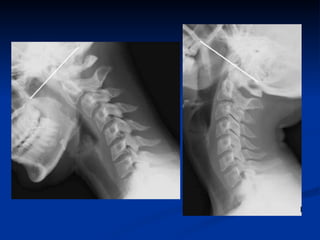

Les incidences de profil en flexion et en extension Patient de profil Position maximale du rachis cervical en extension puis en flexion Etudier les déplacements relatifs de chaque vertèbre.

Les incidences deprofil en flexion et en extension Patient de profil Position maximale du rachis cervical en extension puis en flexion Etudier les déplacements relatifs de chaque vertèbre.